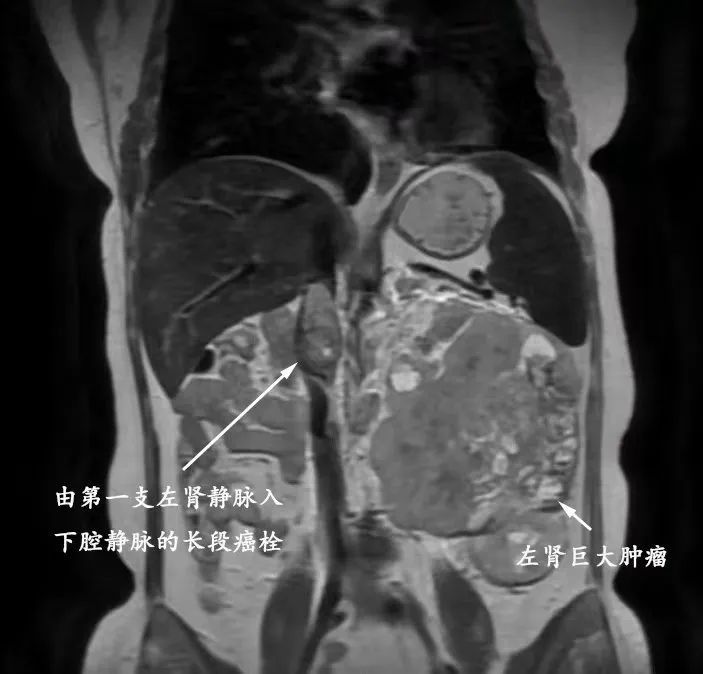

左为腹腔内肿物横断位CT片,右为矢状位CT片

邵远主任仔细阅片后,决定将患者收治入我院嘉定院区泌尿外科病房进行术前评估,同时在肾内科协助下规律透析治疗。我院检查发现,但女士肿物起源于左侧肾脏,体积达11*12.8*11.3cm,几乎填充整个左侧腹部(达T4期),推挤脾胃及同侧肠管。不仅如此,患者有两支左肾静脉,其主干及下腔静脉内均存在长段癌栓(将近Mayo Ⅲ级),一旦癌栓脱落,后果不堪设想。